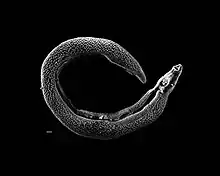

Electron micrograph of an adult male Schistosoma parasite worm. The bar (bottom left) represents a length of 500 μm.

Unlike other flatworms, schistosomes are gonochoristic. The narrow female can be seen emerging from the thicker male's gynecophoral canal below his ventral sucker.